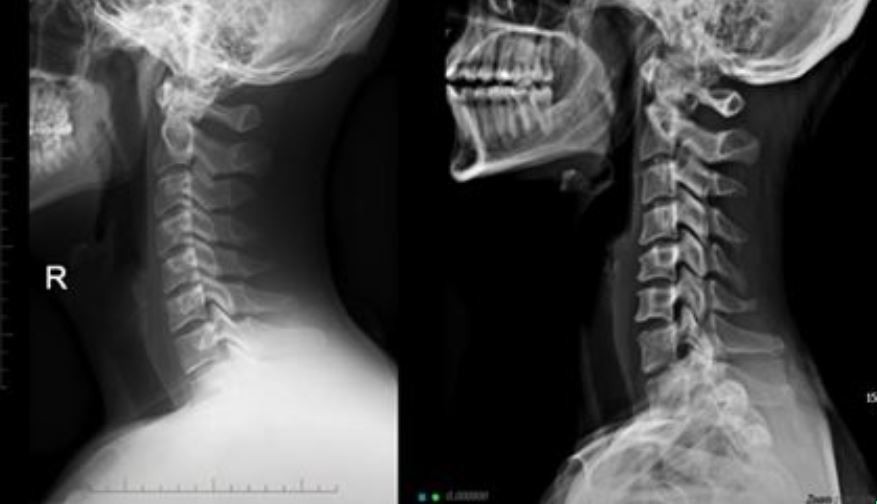

오늘은 목 건강을 위협하는 질환, **목디스크(경추 추간판 탈출증)**의 증상에 대해 이야기하려 합니다. 목디스크는 목뼈 사이에 있는 디스크가 제자리를 벗어나 신경을 압박하면서 발생하는 질환입니다.

- 목 움직임 제한

- 설명: 목덜미 근육이 굳어 고개를 좌우로 돌리거나 뒤로 젖히기 힘듭니다. 목을 움직일 때 뚝뚝 소리가 나거나 뻣뻣한 느낌이 들 수 있습니다.

- 베개 사용: 너무 높거나 낮은 베개는 피하고, 목의 C자 곡선을 유지할 수 있는 기능성 베개를 사용하세요.